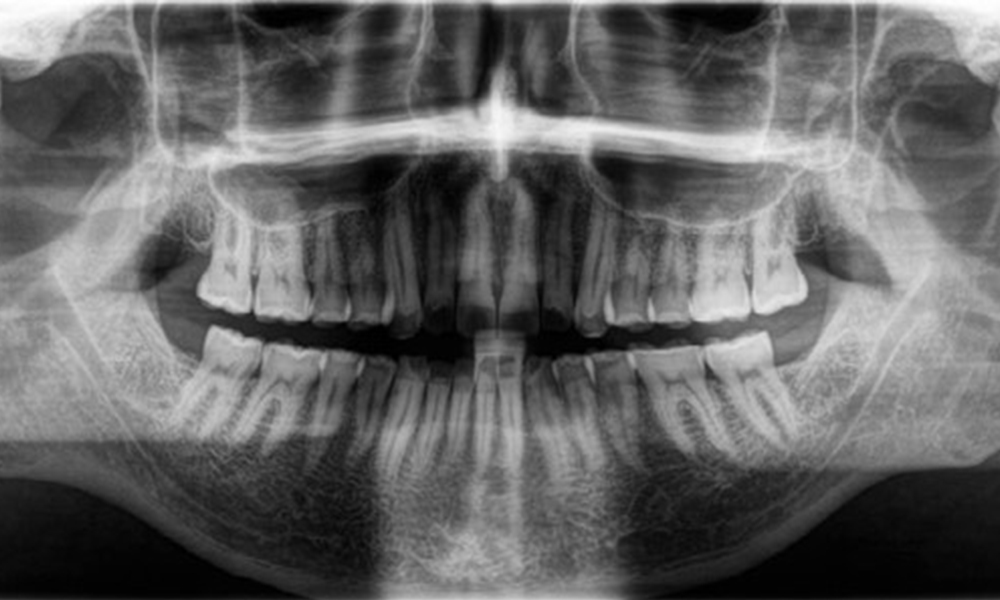

Рентгенологични резултати

Наблюдава се пълноценно съзъбие на постоянните зъби без кариес или рентгенологично разпознаваема загуба на кост (фиг. 6). Рентгенологичната загуба на емайл и туберкул е особено видима при 36 и 37.